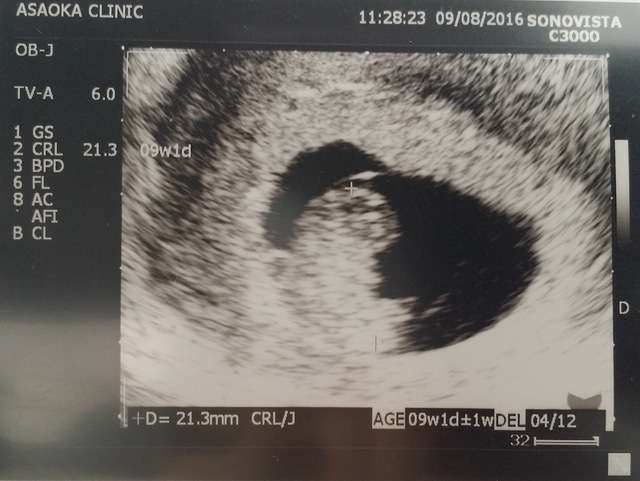

9週1日(9w1d・男の子)|みほみぽ♪ さん(29歳)

エコー写真撮影時のエピソード:

初めての妊娠。2回目の受診でこの姿を見せてくれて、人の形になっていることにとても感動しました!そしてお腹での暮らしを楽しんでいるように見えました(^^)

つわりが辛かったけど、その度にこの写真を見て、元気をもらっていました。